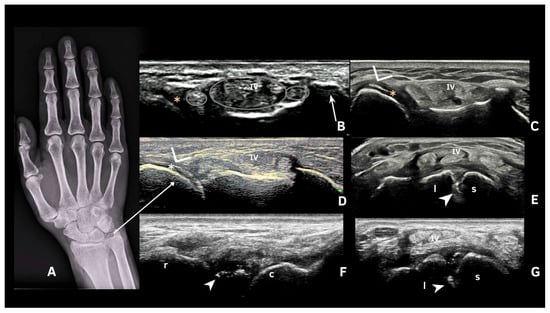

- Cipolletta, E.; Di Matteo, A.; Smerilli, G.; Di Carlo, M.; Di Battista, J.; Abhishek, A.; Grassi, W.; Filippucci, E. Ultrasound findings of calcium pyrophosphate deposition disease at metacarpophalangeal joints. Rheumatology 2022, 61, 3997–4005. [Google Scholar] [CrossRef]

- Cipolletta, E.; Smerilli, G.; Mashadi Mirza, R.; Di Matteo, A.; Carotti, M.; Salaffi, F.; Grassi, W.; Filippucci, E. Sonographic assessment of calcium pyrophosphate deposition disease at wrist. A focus on the dorsal scapho-lunate ligament. Jt. Bone Spine 2020, 87, 611–617. [Google Scholar] [CrossRef]

- Di Matteo, A.; Filippucci, E.; Salaffi, F.; Carotti, M.; Carboni, D.; Di Donato, E.; Grassi, W. Diagnostic accuracy of musculoskeletal ultrasound and conventional radiography in the assessment of the wrist triangular fibrocartilage complex in patients with definite diagnosis of calcium pyrophosphate dihydrate deposition disease. Clin. Exp. Rheumatol. 2017, 35, 647–652. [Google Scholar]

- Forien, M.; Combier, A.; Gardette, A.; Palazzo, E.; Dieudé, P.; Ottaviani, S. Comparison of ultrasonography and radiography of the wrist for diagnosis of calcium pyrophosphate deposition. Jt. Bone Spine 2018, 85, 615–618. [Google Scholar] [CrossRef]

| 1 | Hyperechoic bands, parallel to the surface of the hyaline cartilage |

| 2 | Thin hyperechoic spots in fibrocartilage |

| 3 | Homogeneous hyperechoic nodular or oval deposits in fibrocartilage |

| Fibrocartilage | Shape: Deposits of variable shape. Echogenicity: Hyperechoic (similar to the bone cortex echogenicity). Localization: Within the fibrocartilage structure. Dynamic scanning: Remain fixed and move together with the fibrocartilage during dynamic assessment. Examples: Menisci, TFC, hip labrum, and acromioclavicular joint. |

| Hyaline cartilage | Shape: Deposits of variable shape. Echogenicity: Hyperechoic, without posterior shadowing. Localization: Localized within the hyaline cartilage. Dynamic scanning: The deposits remain fixed and move together with the hyaline cartilage. Examples: Knee and MCP joint. |

| Pseudo-double contour sign | Shape: Deposits of variable shape. Echogenicity: Hyperechoic, without posterior shadowing. Localization: Localized at the chondro-synovial interface or in the joint capsule and adjacent ligaments. Dynamic scanning: Moves in the opposite direction of cartilage and adjacent bone. Examples: Knee, proximal, and distal radio-ulnar joint. |